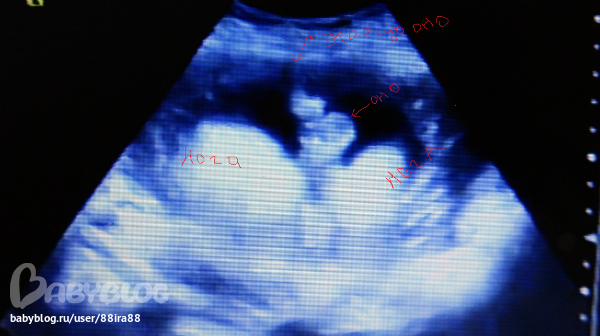

может кто понимает чтото в узи если не трудно посмотрите

первые 7 фото это 19+4 недели

и мне сказали что девочка на 2х узи в 19+4 недель и в 25 недель а вот в 31 сказали кажется мальчик но не точно